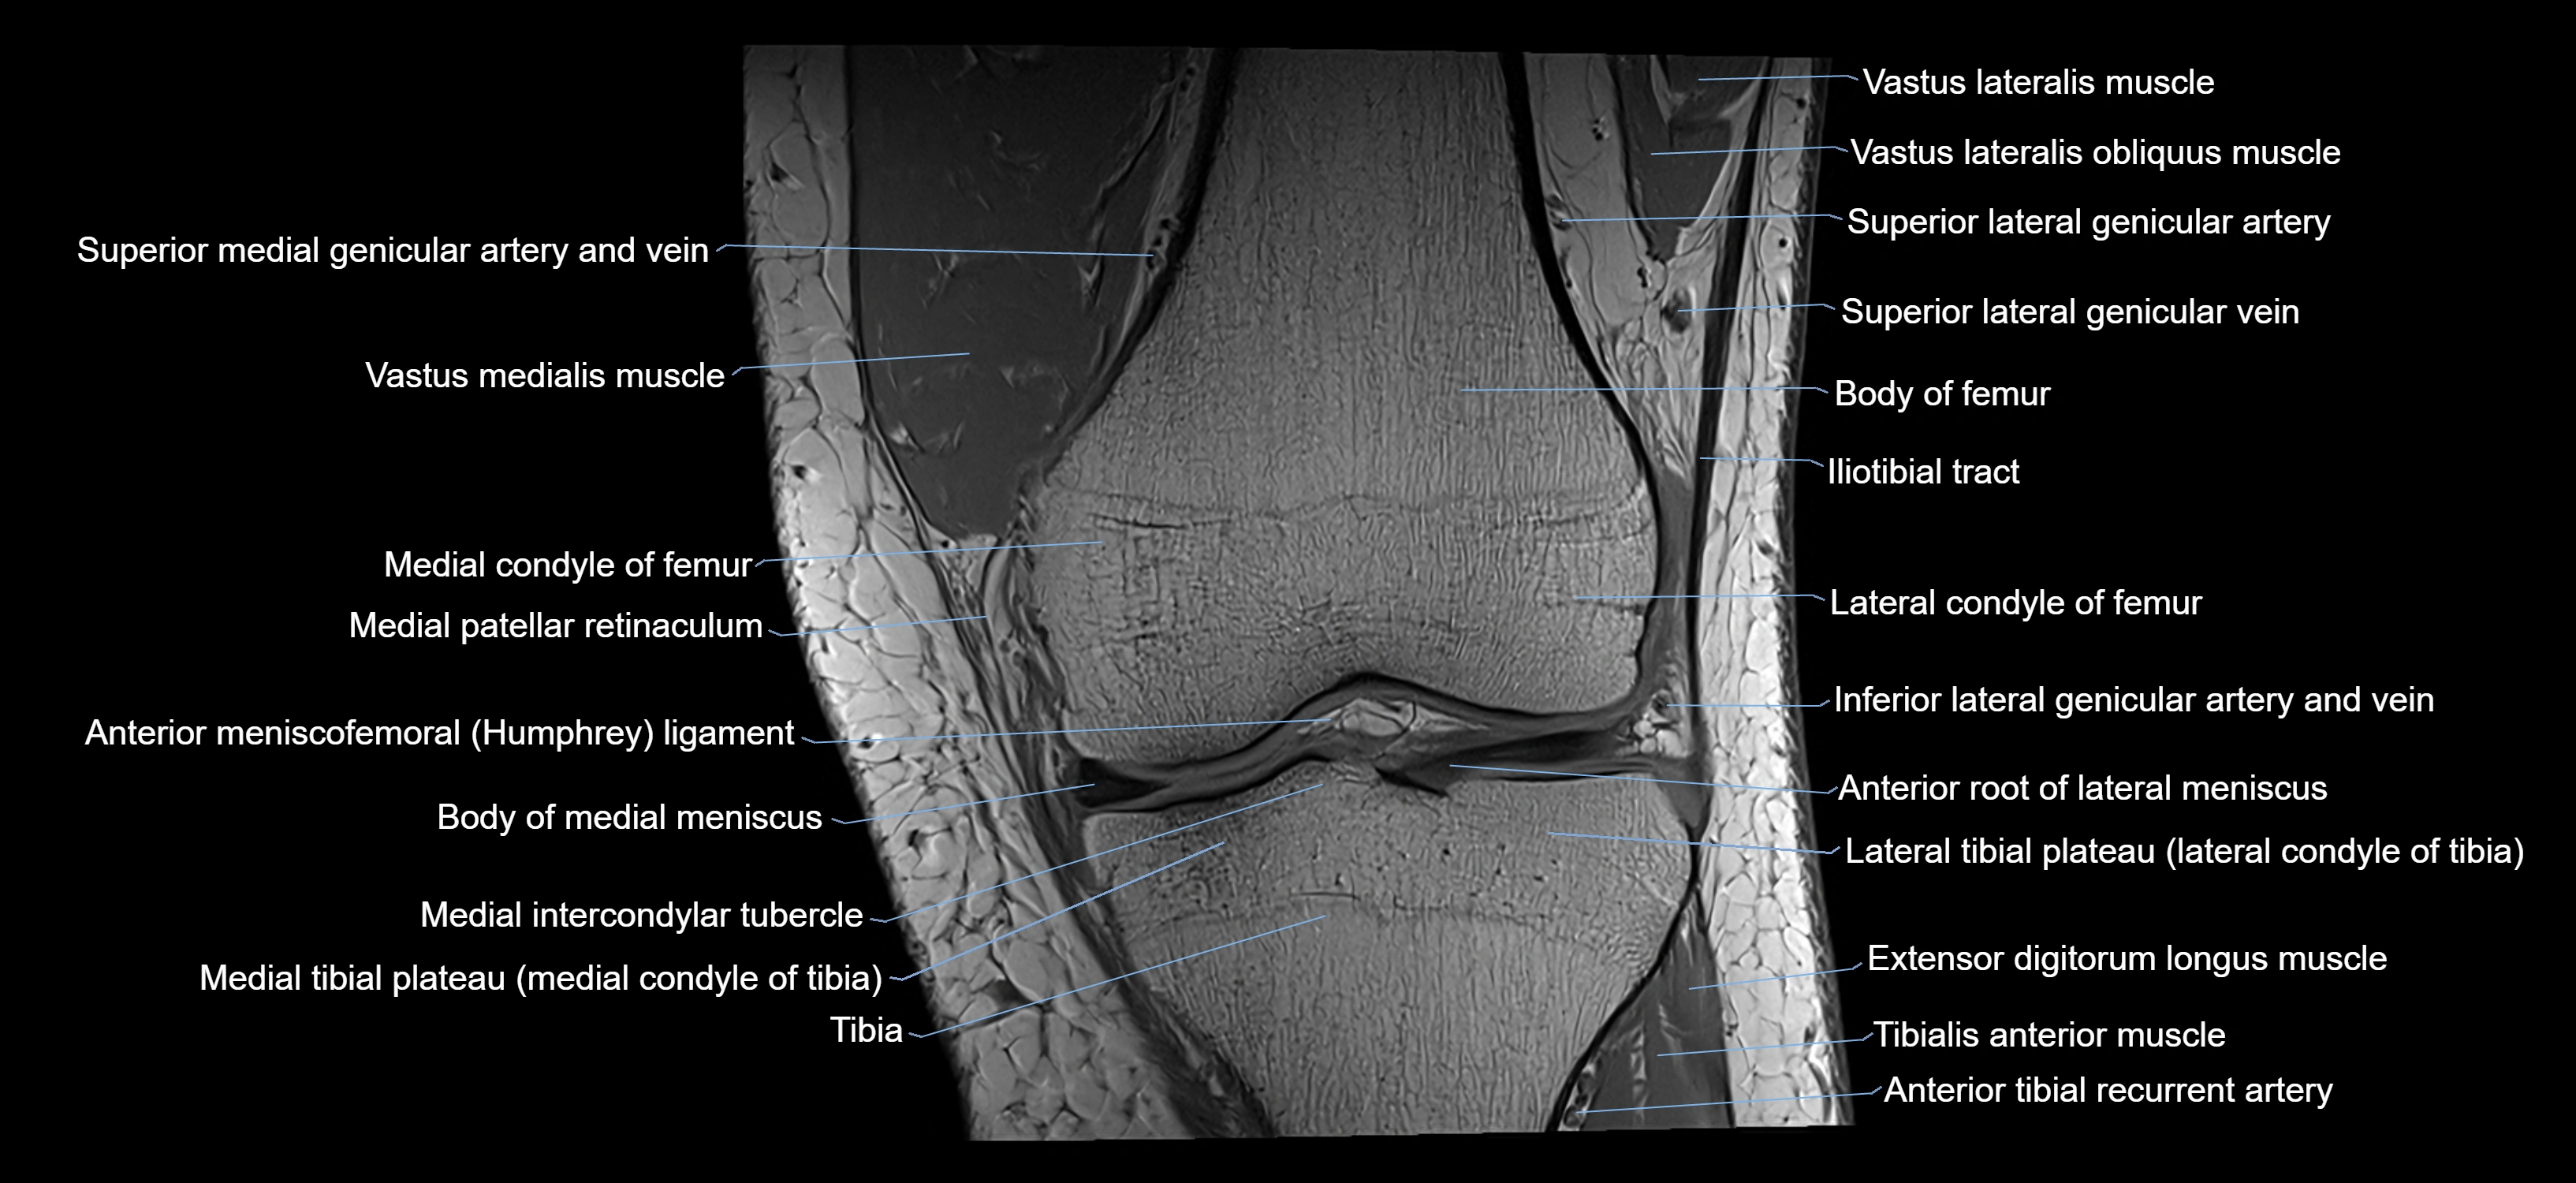

- Knee Joint

- Lateral condyle of femur

- Lateral condyle of tibia

- Lateral tibial plateau

- Medial condyle of femur

- Medial condyle of tibia

- Medial intercondylar tubercle

- Medial meniscus

- Medial patellar retinaculum

- Medial tibial plateau

- Body of medial meniscus

- Anterior root of lateral meniscus

- Anterior meniscofemoral ligament

- Extensor digitorum longus muscle

- Tibialis anterior muscle